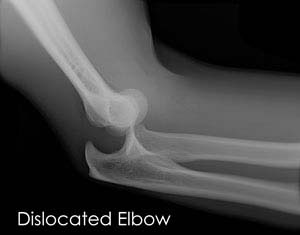

The bones are held together by ligaments to provide stability to the joint. Muscles and tendons move the bones around each other and help in performing various activities. Elbow dislocation occurs when the bones that make up the joint are forced out of alignment.

To diagnose elbow dislocation, your doctor will examine your arm. Your doctor will check the pulses at the wrist and evaluate the circulation to the arm. An X-ray is necessary to determine if there is a break in the bone. An arteriogram, an X-ray of your artery, can be helpful to determine if the artery is injured.